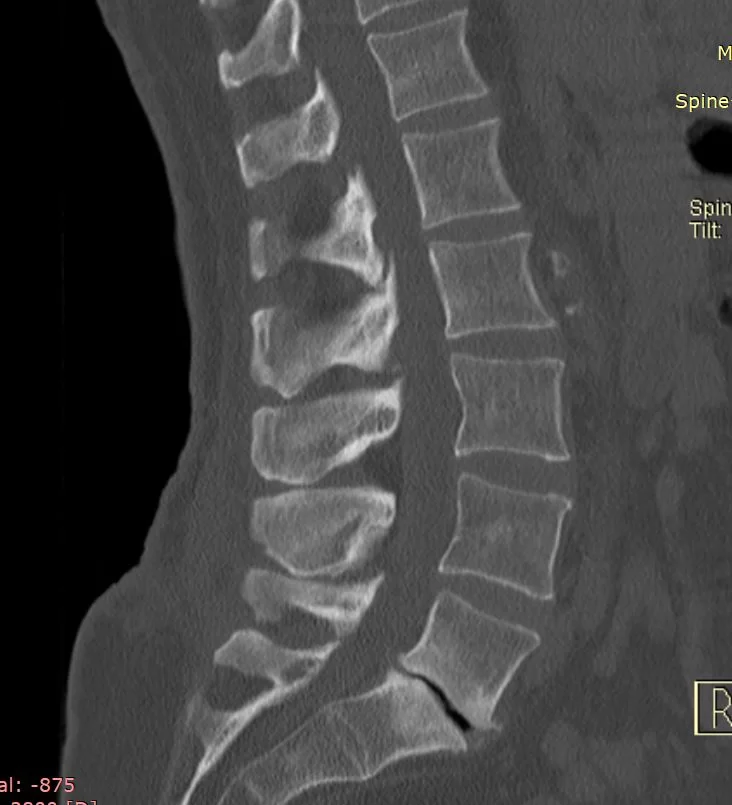

Ο απεικονιστικός έλεγχος ανέδειξε εκφύλιση του δίσκου και εικόνα οστεοαρθρίτιδας στο επίπεδο Ο5/Ι. Στην αξονική διακρίνεται επιπλέον κάταγμα στο δεξιό ισθμό.

Προεγχειρητικές Εικόνες